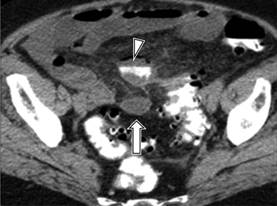

Figura 5: Diverticulitis grado II: TC corte axial muestra engrosamiento de la mucosa (cabeza de flecha) así como absceso pélvico (flecha).